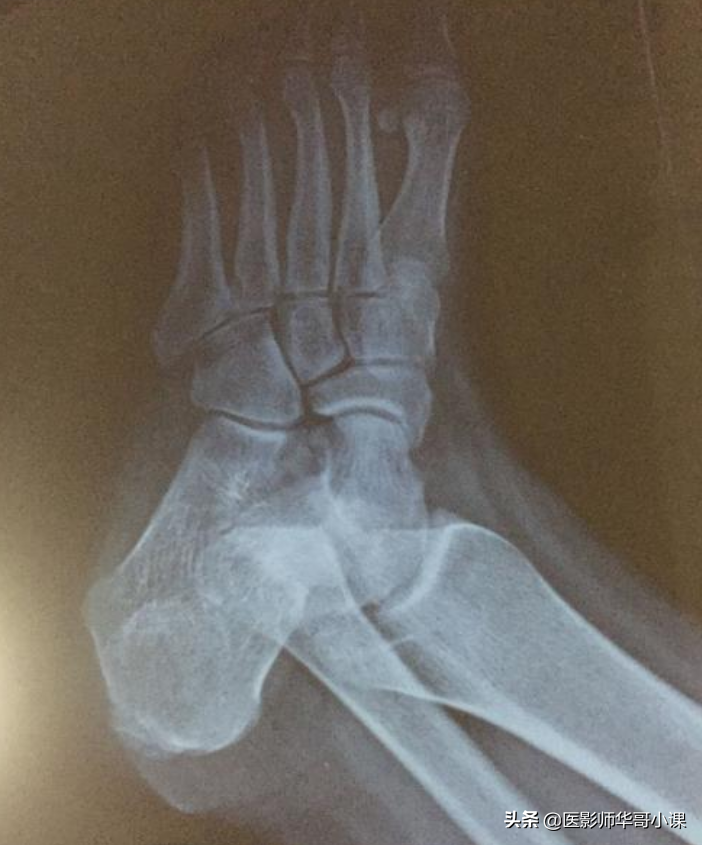

第四节 足与踝

尺骨桡骨怎么区分,怎样分辨尺骨和桡骨(骨关节记忆要点,请收藏)

1趾骨骨骺骨化中心往往为多个小骨化核,外缘不规则。第二,三,五趾末节趾骨骨骺的二次骨化中心可永不出现。

2.末节趾骨的远端稍肥大,边缘不整齐,为正常现象。

3.基节趾骨跖面肌腱附着处,在侧位片上表现为边缘不整齐。

4.趾骨和跖骨,这些小管状骨的继发骨化中心常由若干小骨块组成,在它们出现后若干年内都呈边缘粗糙的不规则阴影,第一趾跖关节处常有一个或两个籽骨,一个籽骨有时可分为两半,不可误为骨折。在发育期间,第五跖骨近端骺软骨外侧可能出现一个阶梯状二次骨化中心,多数为双侧,数年后与跖骨愈合,也可终生不愈合。

5.跖骨近端互相重叠,甚似骨折线,两个跖骨近端可能融合为一,而无跖骨功能不全的症状。

6.跖骨近端可有多余的化骨核,和掌骨一样。

7.舟状骨化骨核发生在生后六个月开始钙化,早期多不整齐或不规则,这种现象可能持续数月或数年之久,仅在一侧发生,在足舟骨结节处的副骨最为多见,一般为双侧性,少数单侧。

8.在舟距关节近端,距骨背缘上的皮雷氏骨,不要误认为碎骨。

9.距骨后结节下缘可能有一副骨即三角骨,这个副骨可能和距骨愈合,也可能是永远分离的。

10.骰骨的化骨核在早期是多个不规则小化骨核,楔状骨的化骨核在早期也可以是不规则的。

11.婴儿和儿童的跟骨后缘是不整齐的,跟骨结节的化骨核最初多为不整形的分节状,以后又较其它部分致密,均为发育中的正常现象。跟骨体偶可有两个独立的或多个骨化中心,二者之间的软骨带在融合前颇似骨折线。

12.跟骨滑车突顶端的二次骨化中心,在外旋和内翻45度角摄片时很似碎骨片。

13.七岁以上儿童的足部侧位上,在跟骨滑车的骨质中能见到一个圆形或三角形的假性囊肿样透亮阴影,此因骨松质稀疏所致。

14.载距小骨足副骨中极其罕见的一种,发生于跟骨载距突的上方。

15.胫骨远端可能出现一个单独分离的内踝化骨核,腓骨外踝部也可有一个单独的化骨核。

16.胫骨骨干远端外侧面面有一条沟槽即腓骨切迹。